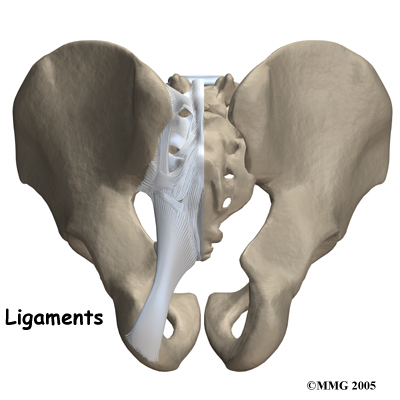

Several large, very strong ligaments hold the SI joint together. The strongest ligaments are in the back of the joint outside of the pelvis. The pelvis is a ring shape so these ligaments work somewhat like the hoops that hold a barrel together. The joint shape and the ligaments are one component in keeping the joint stable; the other component is the force of the muscles. If the ligaments are torn, the pelvis can become unstable.

This sometimes happens when a fracture of the pelvis occurs and the ligaments are also damaged. In most cases of injury to this joint, however, these ligaments are so strong that they are not completely torn unless a great amount of force is involved, such as in motor vehicle accidents.

When ligaments are injured or if they are lax due to hormonal changes (pregnancy) this decreases the stability of the SI joint. As this joint is normally a very stable joint, and requires stability to function, too much relative movement in the joint can cause significant pain and problems. The increased stretching of the abdominal muscles in pregnancy adds to the decreased stability of the joint as the muscles are unable to add as much force to compress the joint.